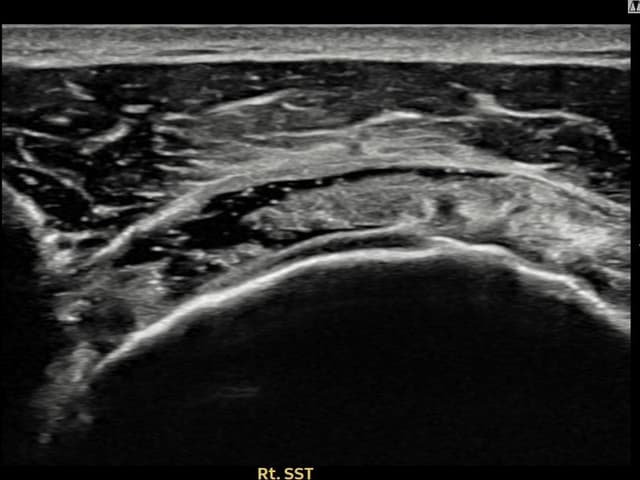

右侧 冈上肌腱 石灰化肌腱炎

10mm × 7mm